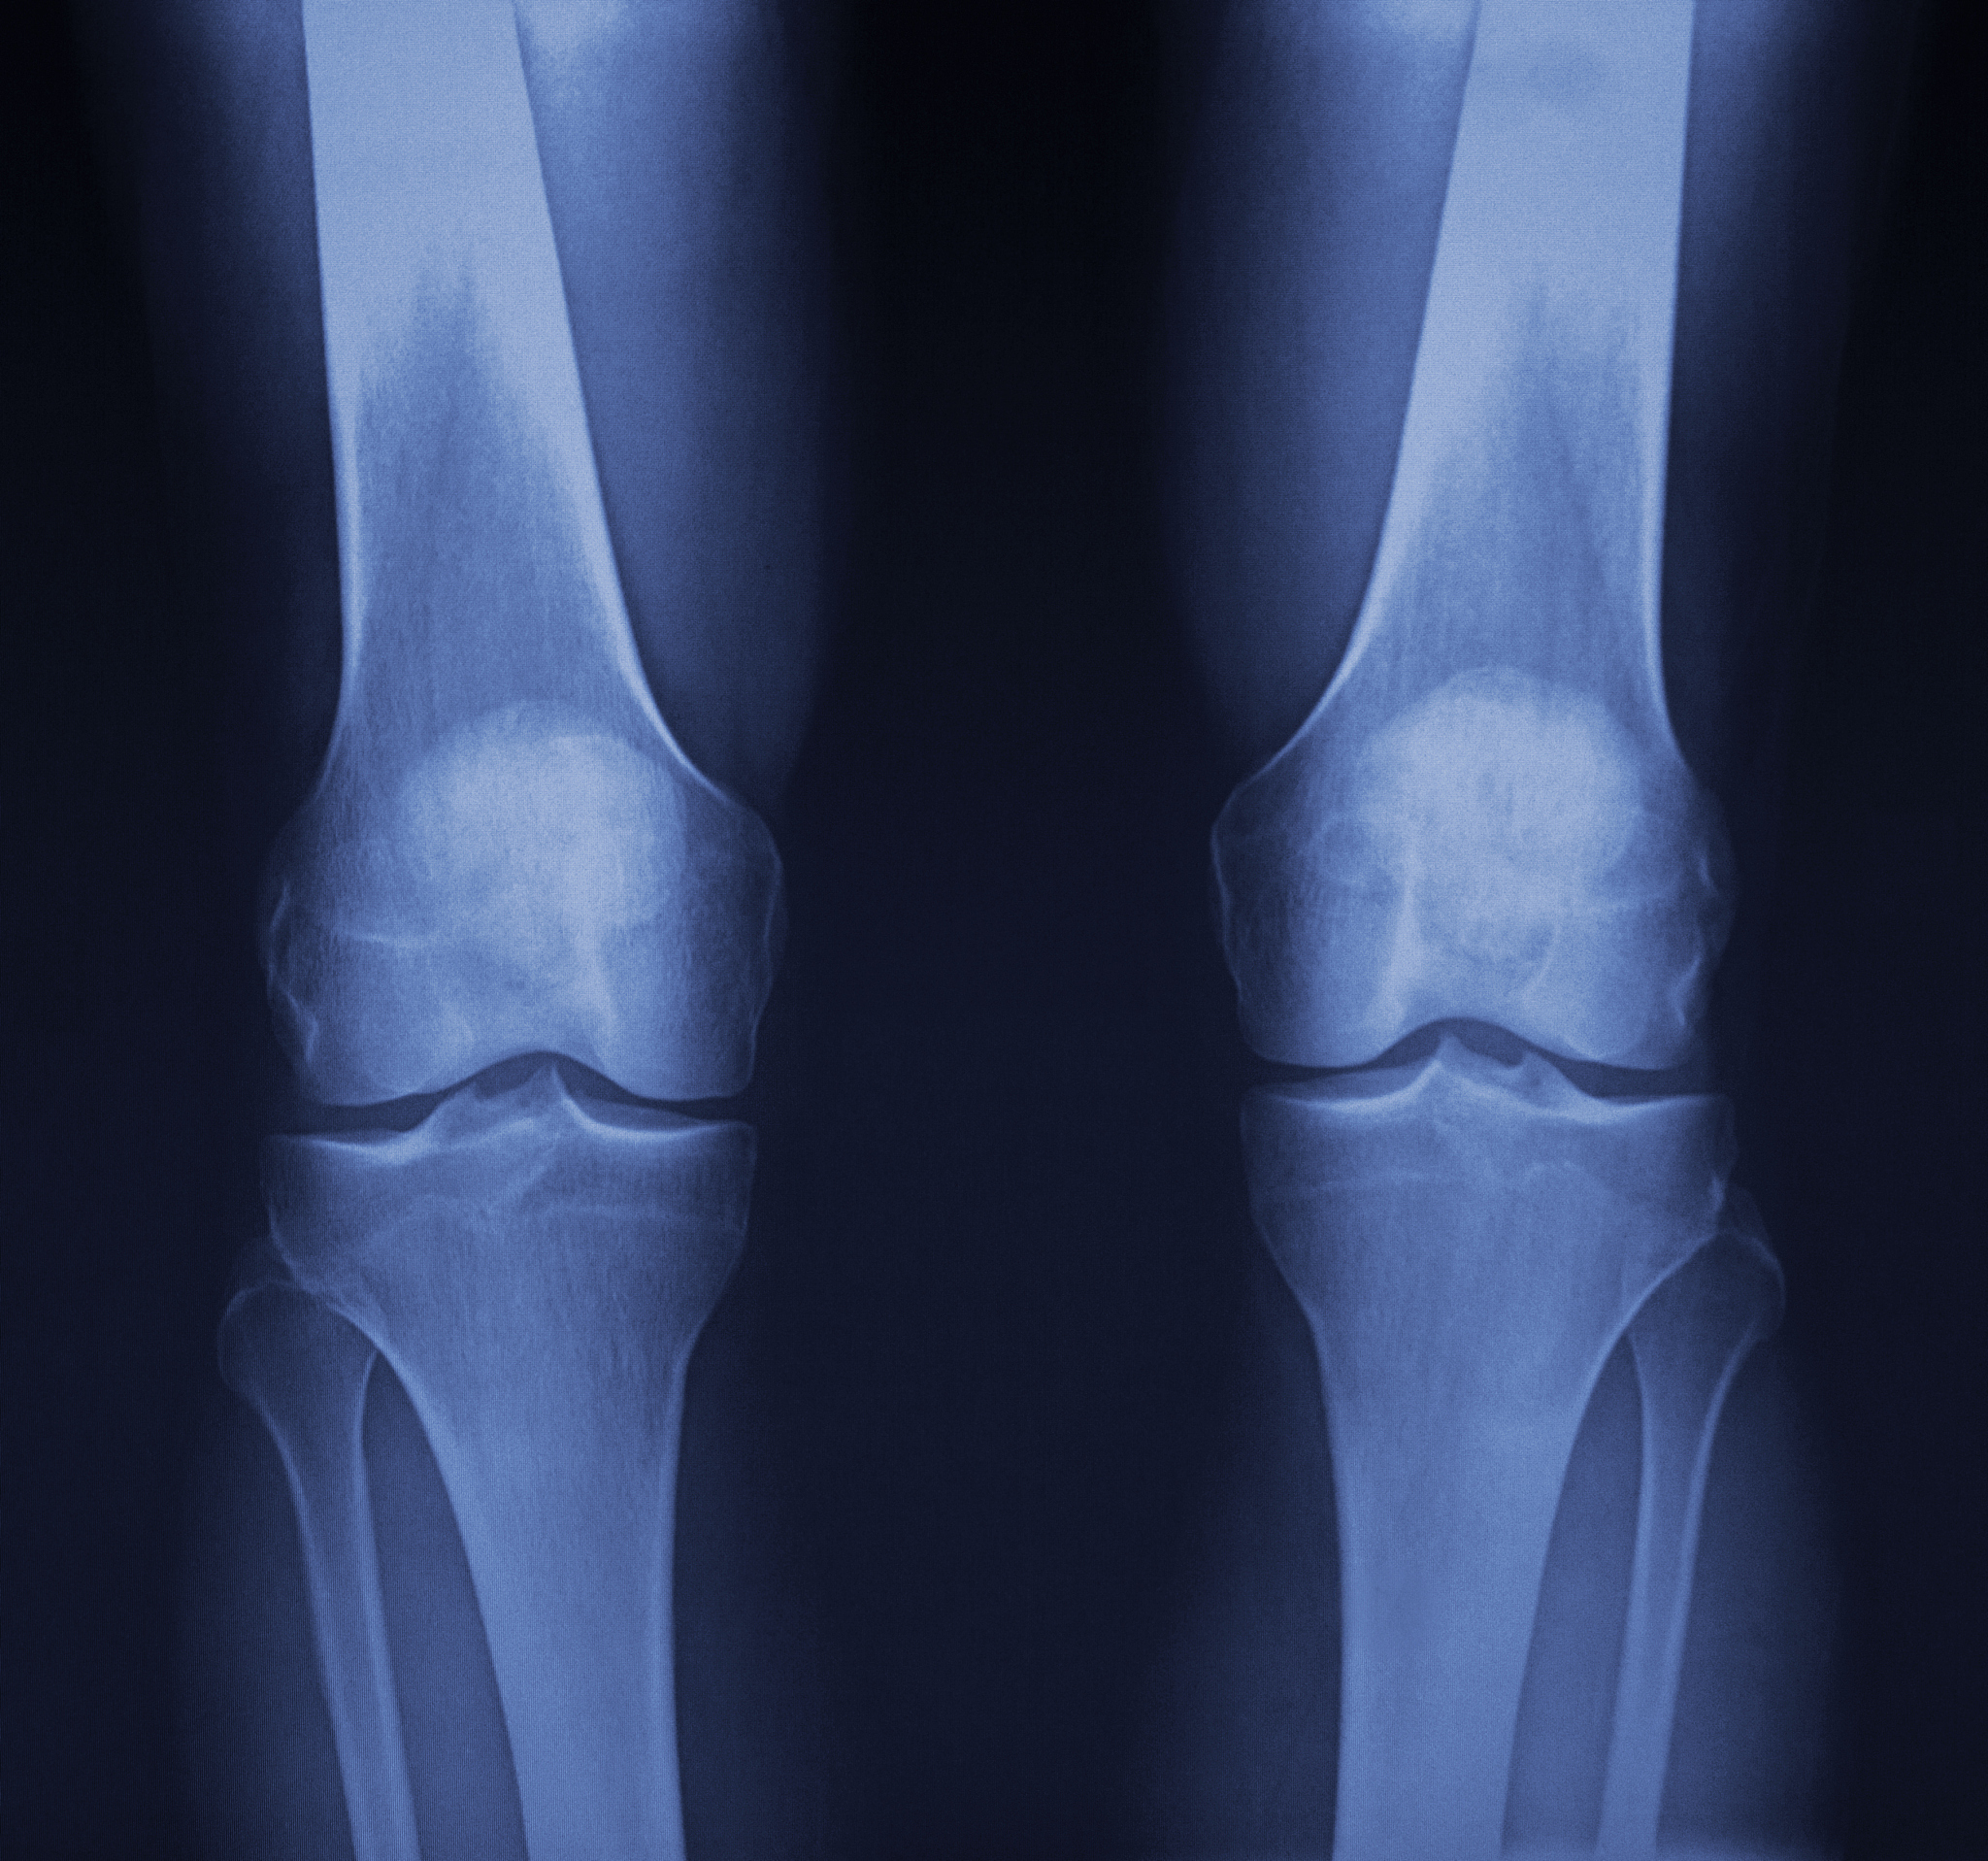

高龄股骨粗隆间骨折是指发生在股骨粗隆和股骨颈之间的骨折,是老年人常见的骨折类型之一。由于老年人骨骼脆弱,这种骨折往往会造成严重影响,甚至导致长期卧床,影响生活质量。